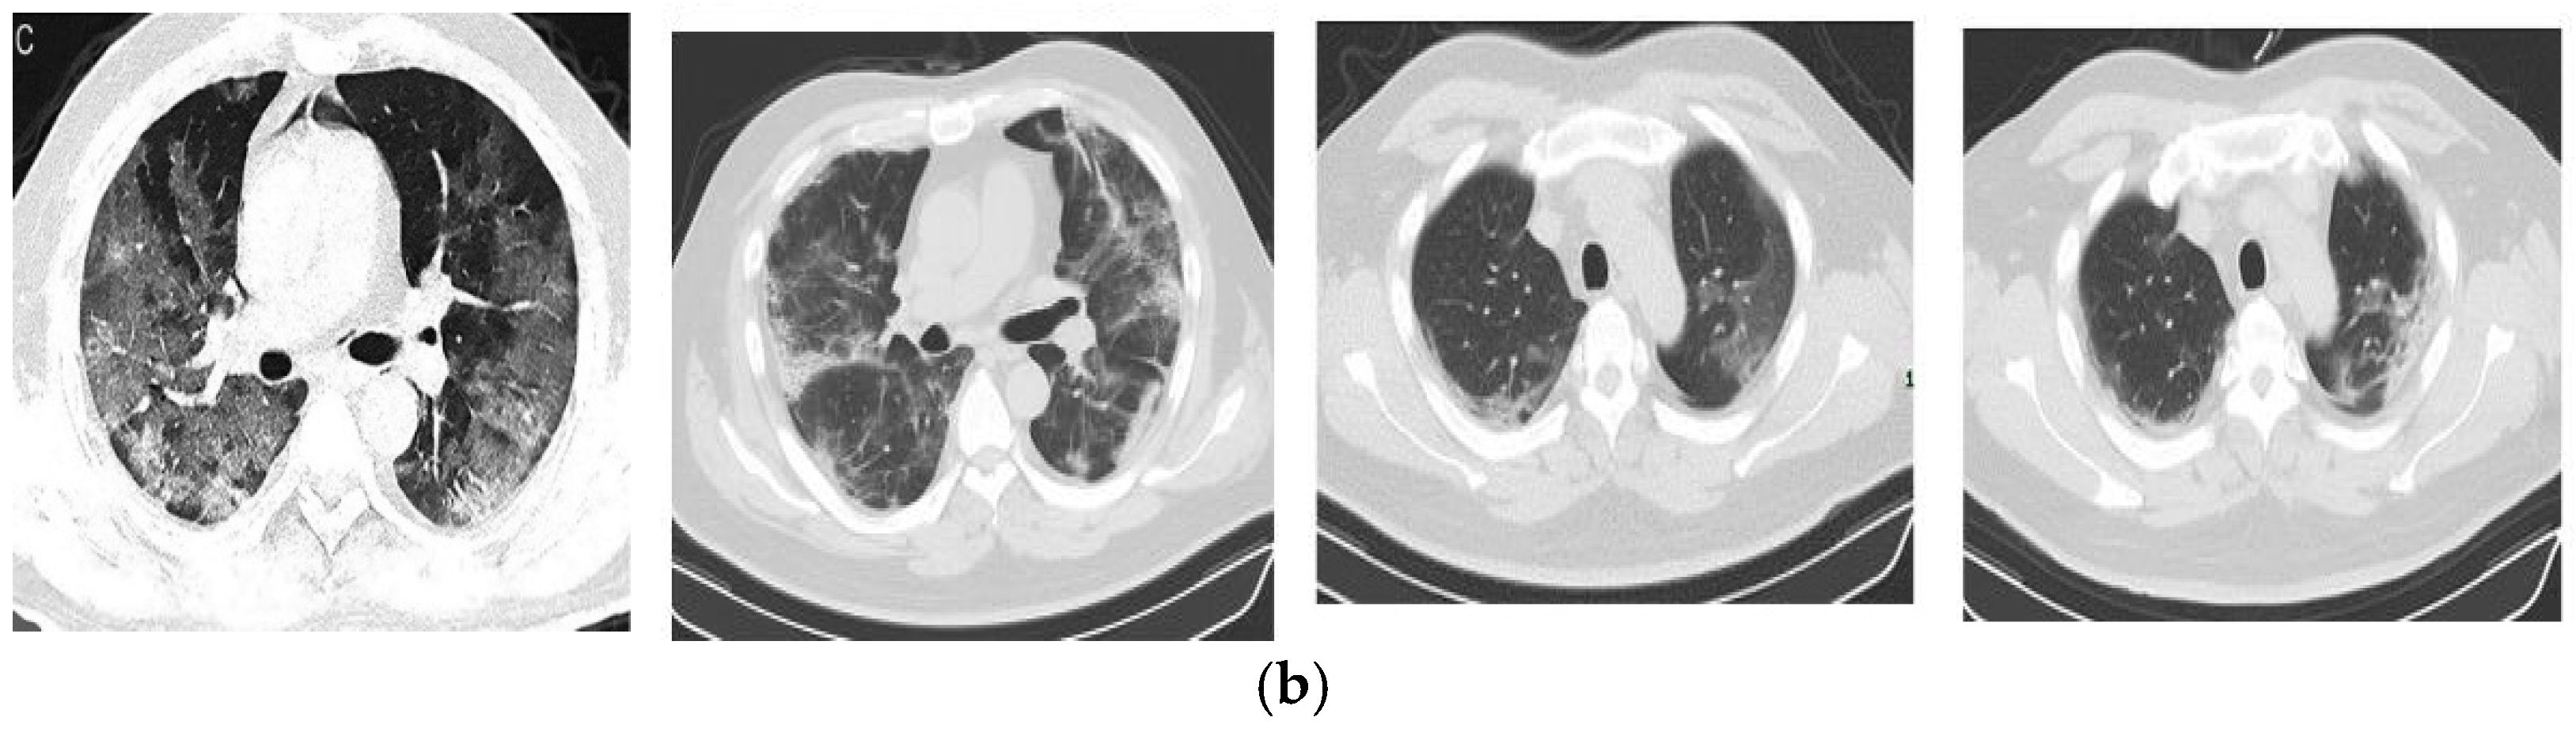

4.1. Datasets

- Zhao, J.; Zhang, Y.; He, X.; Xie, P. Covid-ct-dataset: A ct scan dataset about COVID-19. arXiv 2020, arXiv:2003.13865. [Google Scholar]

- Song, Y.; Zheng, S.; Li, L.; Zhang, X.; Zhang, X.; Huang, Z.; Chen, J.; Zhao, H.; Jie, Y.; Wang, R. Deep learning enables accurate diagnosis of novel coronavirus (COVID-19) with CT images. IEEE/ACM Trans. Comput. Biol. Bioinform. 2021, 18, 2775–2780. [Google Scholar] [CrossRef]

- COVID-19 CT Segmentation Dataset. Available online: http://medicalsegmentation.com/covid19/ (accessed on 10 October 2023).